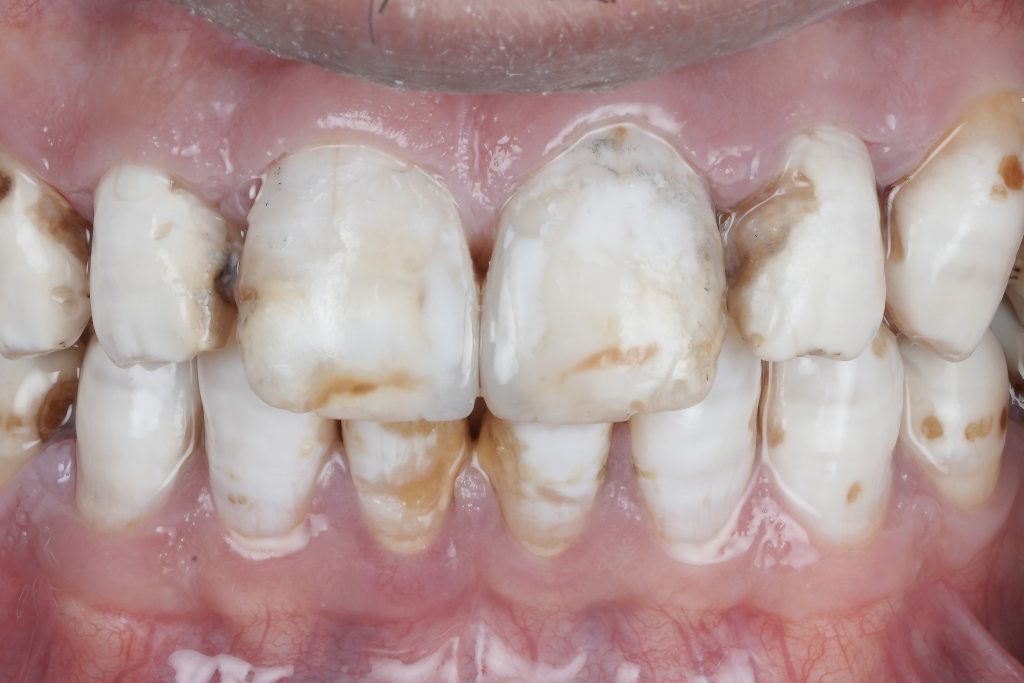

True esthetic dentistry does not begin with restorative materials or ceramic selection. It begins with understanding the condition of the enamel itself. Under proper isolation and magnification, enamel reveals a detailed narrative of demineralisation, developmental defects, discoloration, and marginal compromise that is often masked in routine clinical settings. This article highlights the importance of slowing down, isolating properly, and respecting biological principles to achieve predictable diagnosis, planning, and long-term restorative success.

The Role of Isolation in True Diagnosis

Rubber dam isolation is not merely a moisture-control tool. It is a diagnostic instrument.

Under isolation:

- Saliva-induced gloss is eliminated

- Color distortions caused by hydration are reduced

- Enamel defects become clearly visible

- Margins and transition zones are exposed

Magnification: Seeing What the Naked Eye Cannot

Magnification transforms dentistry from approximation to precision.

Under magnification:

- Enamel prism orientation becomes visible

- Micro-cracks and craze lines can be identified

- Marginal integrity can be assessed accurately

- Adhesive interfaces can be evaluated critically